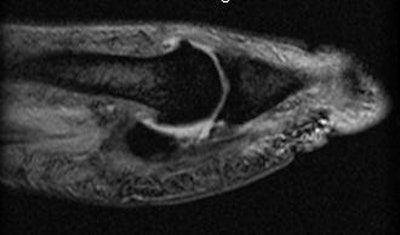

| A case of turf toe. Above, right first MTP sagittal PD image. Middle, first MTP sagittal GRE. Below, first MTP sagittal STIR. |